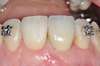

2ème option : sans enfouissement des implants

La gencive est suturée en laissant dépasser la tête des implants. La gencive cicatrise directement autour des implants. Cette technique permet d’éviter un deuxième temps chirurgical pour dégager la tête des implants. En revanche, les implants sont moins bien protégés pendant la période d’intégration osseuse. Cette option est réservée aux cas les plus favorables.